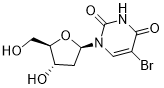

馬鞍山致研生物醫(yī)藥科技有限公司成立于馬鞍山市鄭浦港新區(qū)現(xiàn)代產(chǎn)業(yè)園。公司專(zhuān)注于生物小分子、醫(yī)藥中間體相關(guān)產(chǎn)品的研發(fā)和生產(chǎn),產(chǎn)品主要包括DNA亞磷酰胺單體、RNA亞磷酰胺單體、特殊單體以及按照客戶(hù)要求定制的RNA和DNA,并且公司提供定制合成等方面的研究服...

馬鞍山致研生物醫(yī)藥科技有限公司成立于馬鞍山市鄭浦港新區(qū)現(xiàn)代產(chǎn)業(yè)園。公司專(zhuān)注于生物小分子、醫(yī)藥中間體相關(guān)產(chǎn)品的研發(fā)和生產(chǎn),產(chǎn)品主要包括DNA亞磷酰胺單體、RNA亞磷酰胺單體、特殊單體以及按照客戶(hù)要求定制的RNA和DNA,并且公司提供定制合成等方面的研究服...